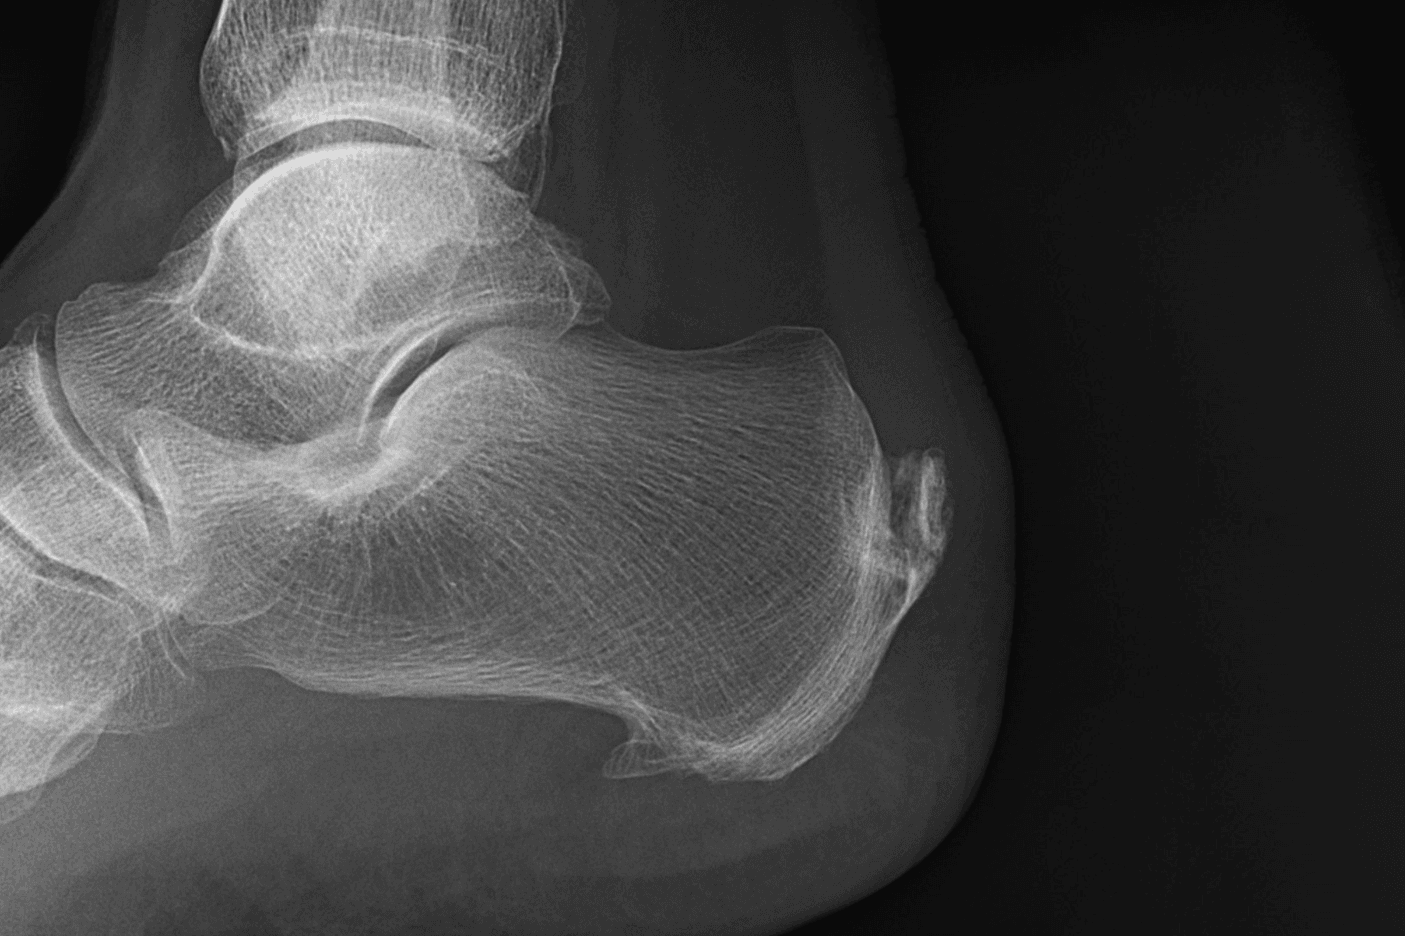

O Prof. Frederico Meirelles fala sobre o Mito do Esporão de Calcâneo e explica a Fascite Plantar. Essas condições são muito comuns nos atendimentos.